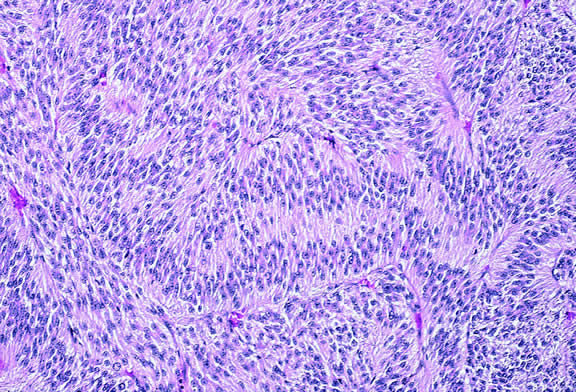

MICROVASCULAR PATTERNS.

Certain microvascular patterns within uveal melanomas have been shown to be prognostic indicators for death from metastatic melanoma.121 Folberg and associates identified nine morphologic patterns of tumor vessels in eyes removed for ciliary body or choroidal melanoma and designated them: (1) normal, (2) silent, (3) straight, (4) parallel, (5) parallel with cross-linking, (6) arcs, (7) arcs with branching, (8) loops, and (9) networks. The presence of vascular loops and microvascular networks composed of back-to-back loops that encircle microdomains of tumor are strongly associated with death from metastatic melanoma122 (Fig. 45). Prognostic vascular patterns appear to be consistent throughout the depth of a tumor, and the cross-sectional area occupied by prognostic microvascular patterns also has prognostic value.123,124 Additional studies from Folberg's laboratory have compared the microcirculation architecture of nevi and melanomas125 and examined the relationship between microvascular architecture and the aggressive behavior of ciliary body melanomas.126 Attempts to detect prognostically significant microcirculatory patterns in vivo using noninvasive imaging techniques including ultrasonography127,128 and confocal angiography with fluorescein or indocyanine green have been made.129,130 A study of 496 posterior uveal melanomas at the AFIP confirmed that the presence of loops did indicate poor outcome but was not as good a prognostic indicator as the mean diameter of the largest nucleoli, cell type, or tumor size.131

Fig. 45. Networks of vascular loops, uveal melanoma. Fibrovascular septa divide parts of this predominantly epithelioid melanoma into roughly circular zones called vascular loops. Vascular networks are composed of adjacent vascular loops. Uveal melanomas that contain vascular loops and networks have a poorer prognosis. (Hematoxylin-eosin, × 50.)